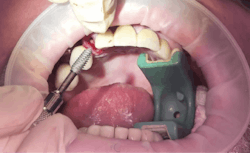

Another reason immediate placement is advantageous is that once the extraction is complete, the hole is usually already in the proper place for the implant. You may have to redirect your osteotomy slightly palatally, mesially, or distally, but the socket serves as an excellent guide for placement. In some cases, especially premolars, you can use an implant with aggressive threads to place without any osteotomy at all. You can engage the mesial and distal walls to achieve primary stability. This greatly shortens the appointment time, lowers risk, and increases patient satisfaction. Figures 1 and 2 show a MorsTorq in site No. 21 that was placed after an atraumatic extraction during my most recent two-day Louisiana Implant Institute course. Note the sharp threading on the MorsTorq, which allows for optimized immediate placement performance.There are some circumstances where immediate placement is not desirable. If the socket is too large to engage the mesial and distal walls and vital anatomical structures are located just apical to the socket, immediate placement is not recommended. Chronically infected sites also present a higher risk for immediate placement. If you can completely rid the socket of all soft tissue and the patient has the appropriate antibiotics onboard, it is possible. However, most of these cases are more predictably treated with early placement (waiting four to six weeks without grafting) or delayed placement (three to six months with grafting).

When placing an immediate implant, you must maintain a gap of at least 2 mm between the implant and buccal wall to prevent resorption of the plate and thread exposure.Next in the series